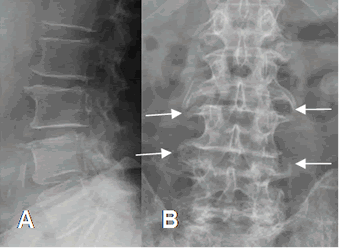

Fig 46. Sindesmofitos.

A: Rx lateral y B: Rx AP lumbar. Múltiples osteofitos lumbares, con formación de sindesmofitos.